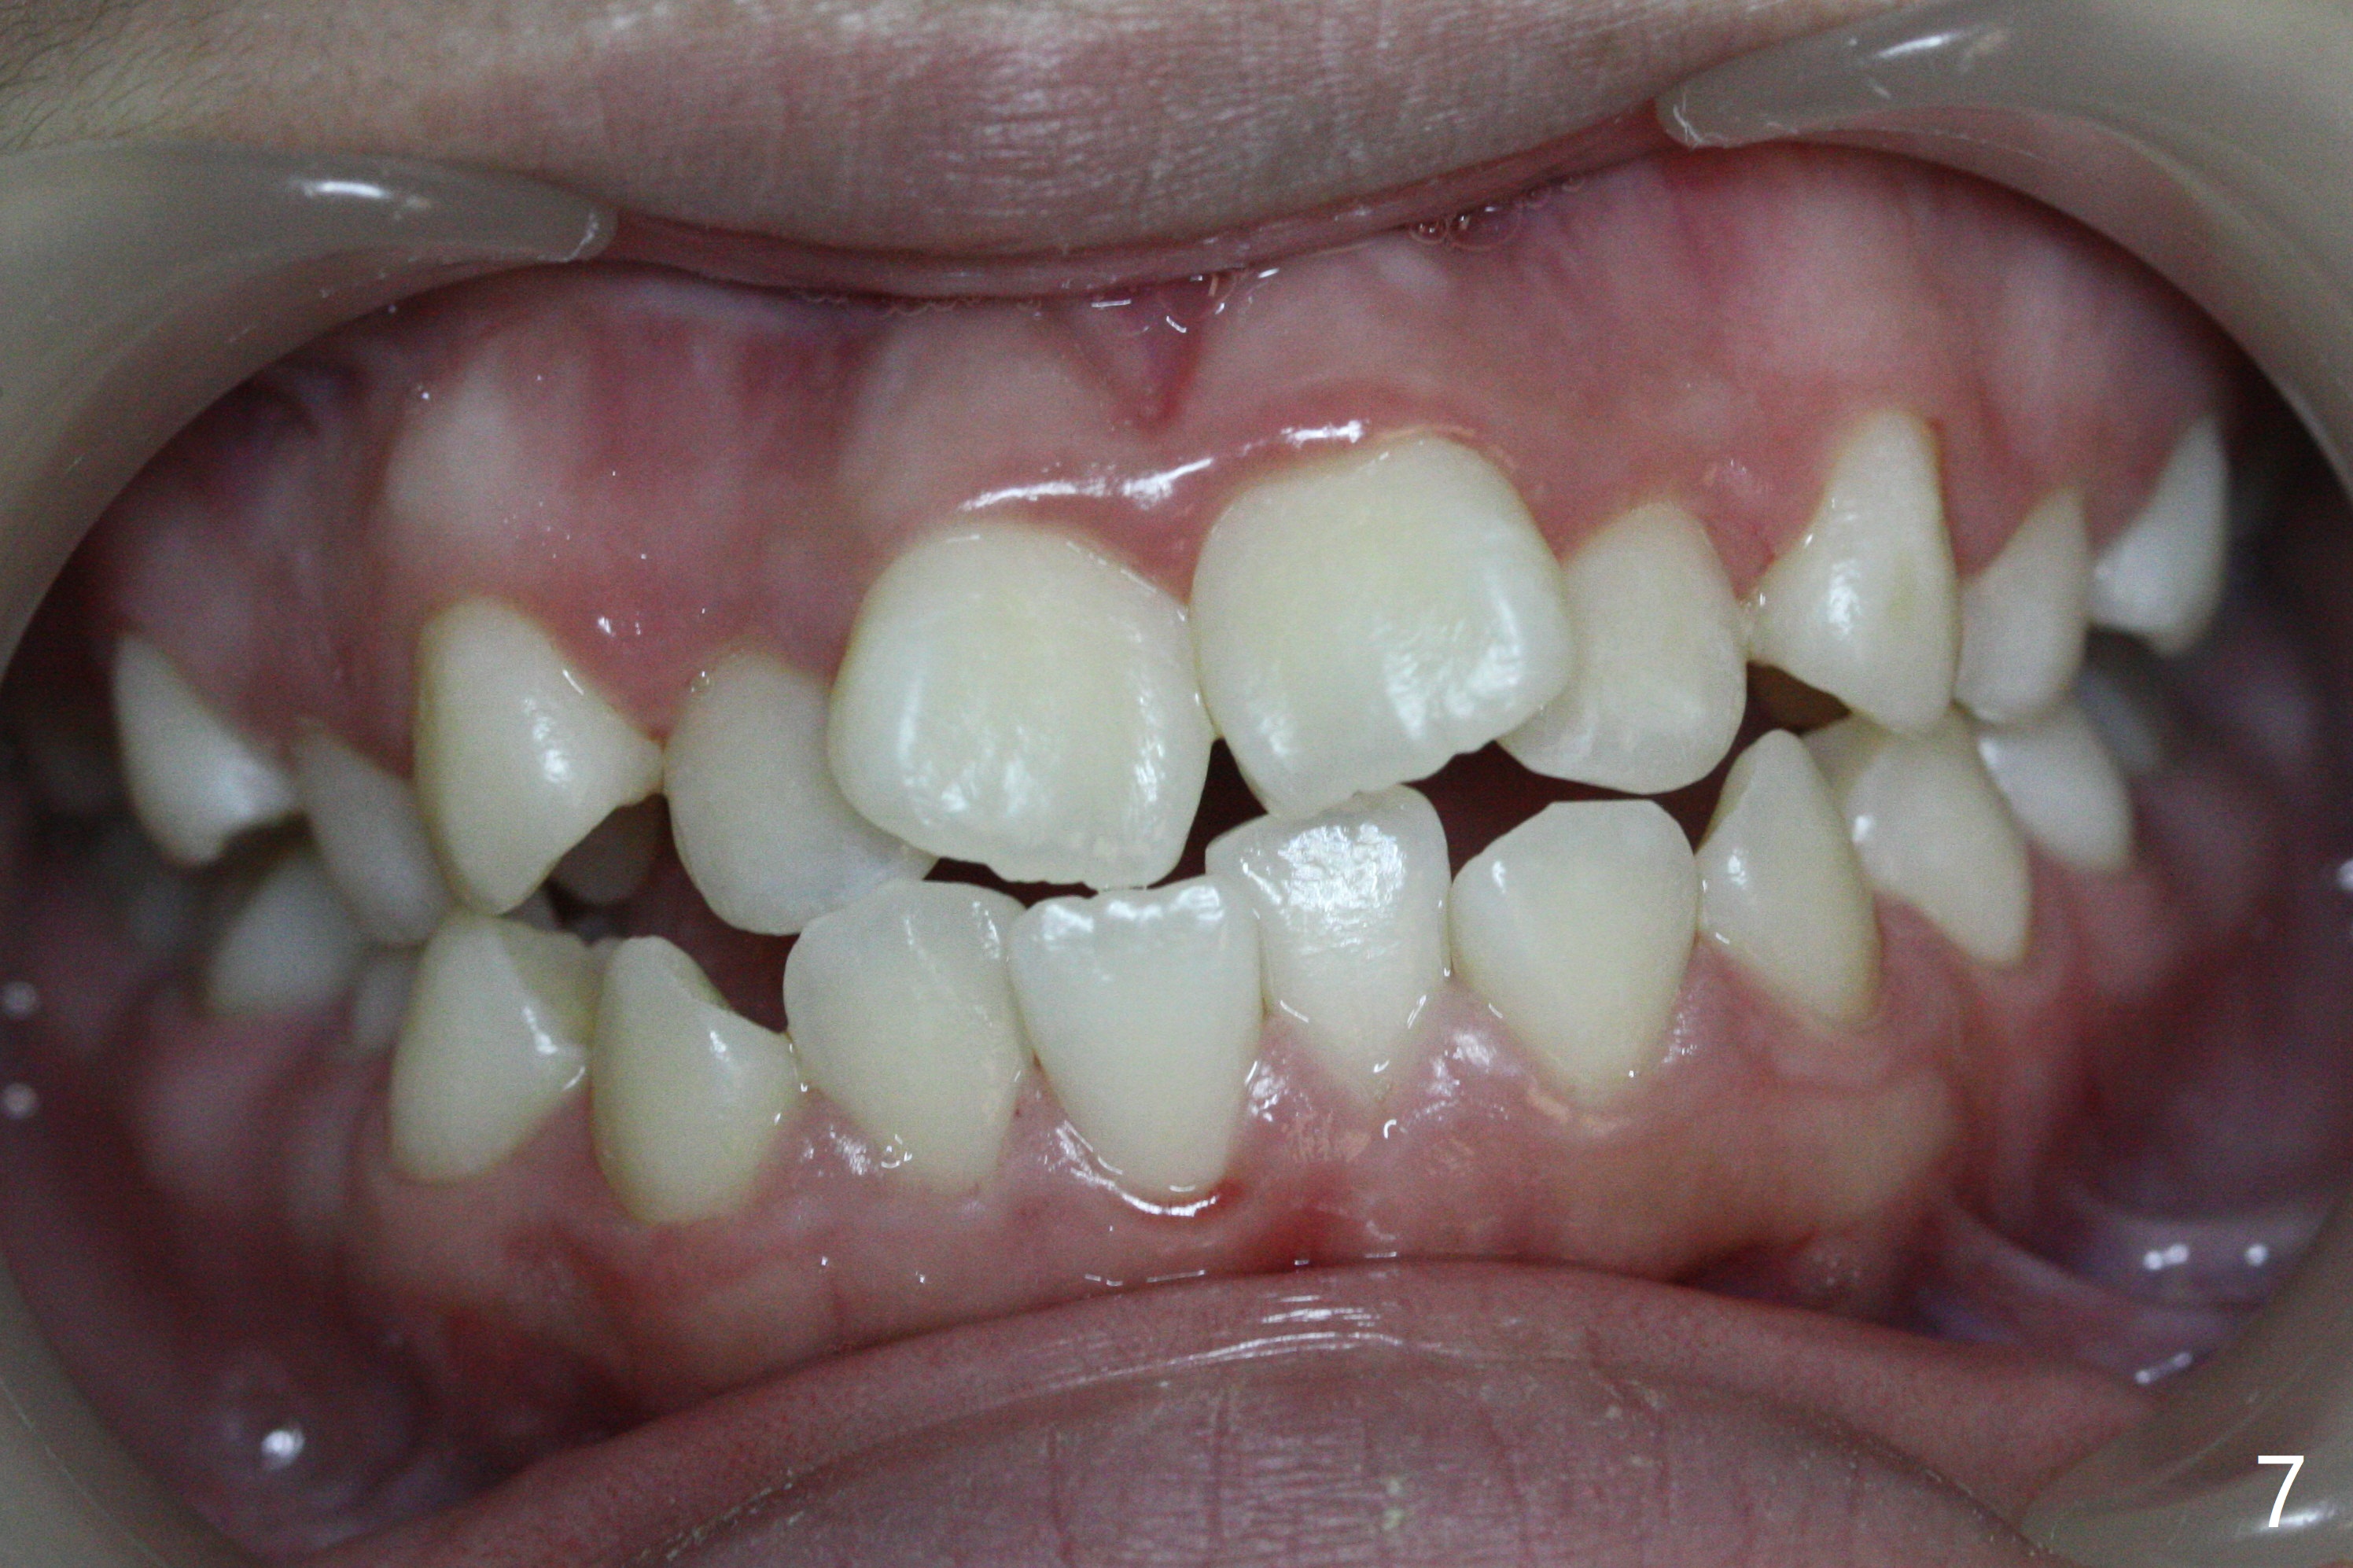

A 14-year-old woman has convex facial profile (Fig.1-4) with the upper midline shifted to the left (Fig.2). Since the roots of the 1st bicuspids are short (Fig.5), extraction should be easy. U3 will be retracted distal early with intention to correct the upper midline. With Class I occlusion at the canines and the 1st molars and good initial interdigitation (Fig.6-11), orthodontic treatment should be rewarding. Because of severe crowding (tight contact, Fig.12,13), place separators after extraction and place bands and brackets a few days later. Cephalometric analysis (Fig.14) shows that SNB is greater than SNA (82.4 vs. 81.8 degree); after extraction, retract the lower anterior teeth prior to the upper ones. It is easy to place separators after extraction (Fig.16,17).